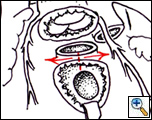

The pulmonary artery is transected proximally, the pulmonary valve is resected and the conal septum divided (Figure 1, right). The aortic root is then translocated posteriorly and sutured to the pulmonary valve annulus posteriorly (Figure 2, left) and to the crest of the VSD (or the VSD patch) anteriorly (Figure 2, right). The coronary arteries, if detached, are then reimplanted.